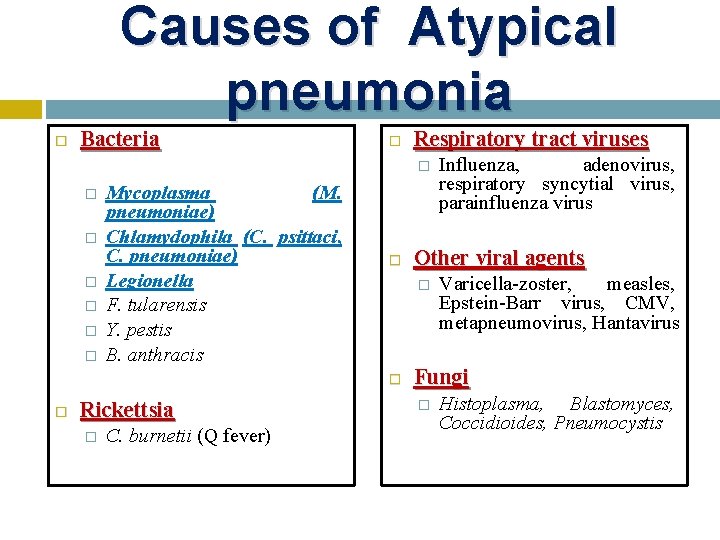

Causes of Atypical pneumonia Bacteria Respiratory tract viruses � � � � Mycoplasma (M. pneumoniae) Chlamydophila (C. psittaci, C. pneumoniae) Legionella F. tularensis Y. pestis B. anthracis Rickettsia � C. burnetii (Q fever) Other viral agents � Influenza, adenovirus, respiratory syncytial virus, parainfluenza virus Varicella-zoster, measles, Epstein-Barr virus, CMV, metapneumovirus, Hantavirus Fungi � Histoplasma, Blastomyces, Coccidioides, Pneumocystis